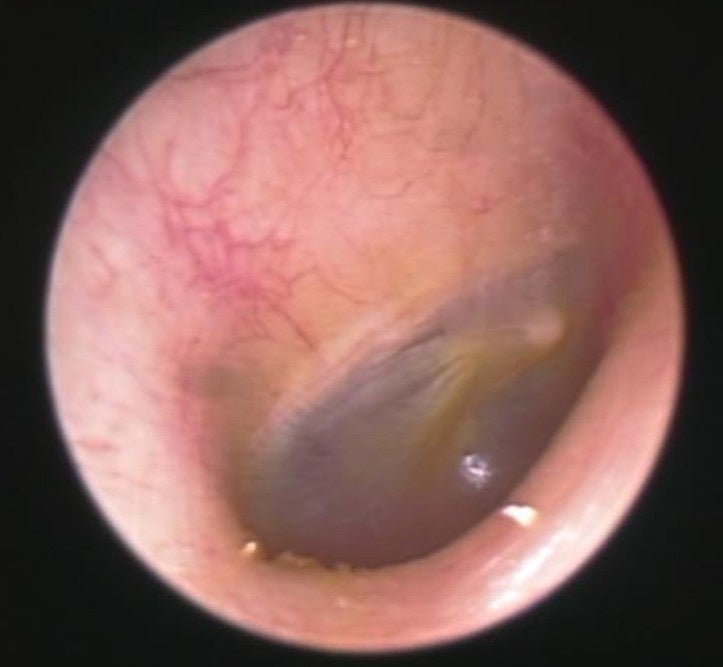

■外耳炎や外耳道真菌症(耳カビ)についても解説

『外耳炎は、耳の入り口から鼓膜までの「外耳道」と呼ばれる部分の皮膚に細菌が繁殖しておきる病気です。真菌(カビ)が繁殖すると、外耳道真菌症(耳カビ)になります。発症リスクが上がる原因のひとつとして「密閉型イヤホンの長時間使用」が挙げられます。

主な症状は、かゆみ、痛み、耳が詰まったような感じ、聞こえにくさです。特にかゆみは薬で治療しないとサイクルから抜け出せません。温度が20~30度、湿度が60%以上、風通しが悪く日陰だとこのようなカビが繁殖することがあります。密閉型のイヤホンを長時間装着すると、このようなカビができるリスクが高まります。治療法として、外来でカビを掃除して薬を塗ることを繰り返し行いますが、1ヶ月~数ヶ月かかることも稀ではありません。

耳のトラブルを放置すると、治りにくくなる、聴力が低下する、さらに悪化してしまい中耳や内耳、悪性外耳道炎などの重篤な病気が進行してしまう場合もあります。痒みや違和感は無理せずケアをしましょう。』と医師の観点から解説していただきました。